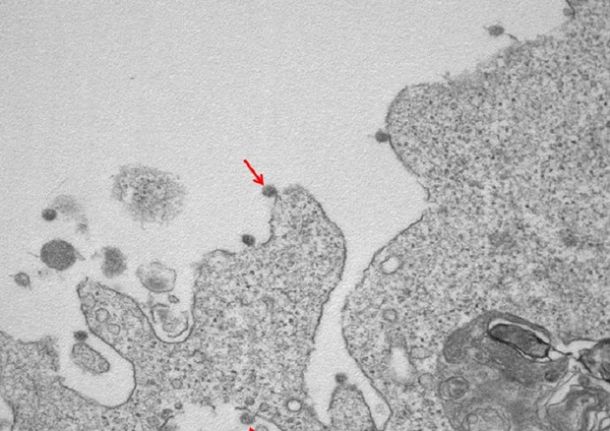

ROMA – Si vede anche la famosa ‘corona’, nel primo ritratto in bianco e nero del virus SarsCoV2 isolato in Lombardia all’Ospedale Sacco di Milano: le immagini al microscopio elettronico mostrano le particelle virali adese alle membrane delle cellule e la loro tipica corona di glicoproteine superficiali. L’annuncio in una nota dell’Università Statale di Milano.

Nella prima, a un ingrandimento di 30000X, si osservano le particelle virali di SarsCov2 (indicate dalle frecce), adese alle membrane sulla superficie e all’interno di cellule utilizzate per l’isolamento.